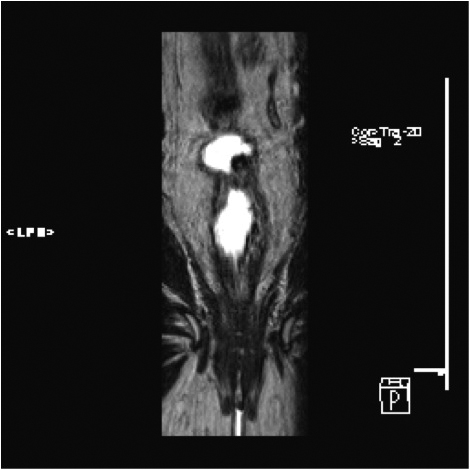

Fig1. Pacient cu neoplasm rectal stadiul IIIC (T3; N2; M0) confirmat bioptic, adenocarcinom mixt G2

a-d imagini T2 ponderate în plan sagital, oblic axial și oblic coronal – masă tisulară dezvoltată superior de joncțiunea anorectală, lateral dreapta, cu minimă extensie la nivelul grăsimii mezorectale și limfoganglioni mezorectali cu diametru de până la 10 mm;

j) reconstrucții curbe în planul adevărat al rectului, cu evidențiere mai bună a fasciei mezorectale